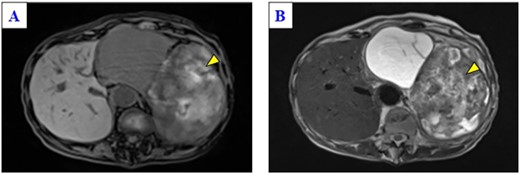

A 79-year-old woman was referred to our hospital because of nausea for about 3 months. Her medical and family histories were unremarkable. On admission, her vital parameters were as follows: temperature, 36.6°C; blood pressure, 120/84 mmHg; heart rate, 72 beats per minute (regular); respiratory rate, 15 breaths per minute and oxygen saturation, 99% on room air. Physical examination revealed a soft mass was palpable in the left upper quadrant. Laboratory investigation revealed slight anemia (hemoglobin: 10.3 g/dL), but other results, including the serum tumor markers carcinoembryonic antigen, cancer antigen 19-9 and cancer antigen 125, were within normal ranges. Abdominal computed tomography (CT) revealed a large tumor with multilocular cystic and solid components, and only a small amount of normal splenic parenchyma remained. And the tumor extensively compressed the stomach ventrally. The boundary between the pancreatic tail and the hilum of the spleen was somewhat unclear, but no obvious mass lesion was observed in the pancreas (Fig. 1A and B). On magnetic resonance imaging, the solid part included an uneven high signal on T1-weighted images and a low signal on T2-weighted images, suggesting internal bleeding (Fig. 2A and B). On a positron emission tomography scan, 35.9 points of 18F-fluorodeoxyglucose accumulation of standardized uptake value showed in the only solid part of the tumor (Fig. 3). Although a definitive preoperative diagnosis could not be made, angiosarcoma originating in the spleen was suspected first, and laparotomy was performed.

Magnetic resonance imaging of the solid part of the tumor shows a heterogeneous hyperintense area in a T1-weighted image (A) and a hypointensity area in a T2-weighted image (B) (yellow arrows).